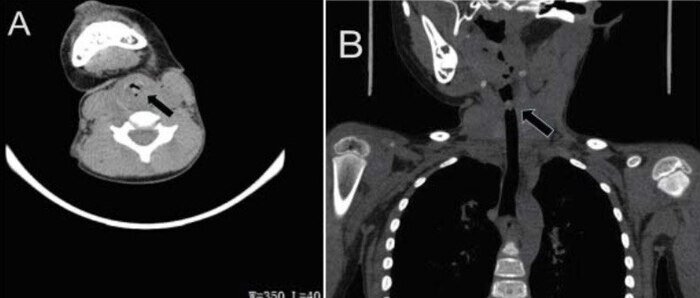

У ранее здоровой 4-летней девочки в течение 10 дней наблюдались хрипы, затрудненное дыхание и кровохарканье, а ранее 20 дней назад со слов мамы из полости носа выпала живая пиявка. При физикальном осмотре никаких отклонений отмечено не было. Компьютерная томография грудной клетки (КТ) показала наличие инородного тела на задней стенкой трахеи на уровне шестого и седьмого шейных позвонков.

Ей была проведена операция по удалению инородного тела из трахеи под общим наркозом с использованием эндоскопического оборудования. Инородное тело было обнаружено субглоттально на задней стенке трахеи, объект был идентифицирован как живая пиявка.